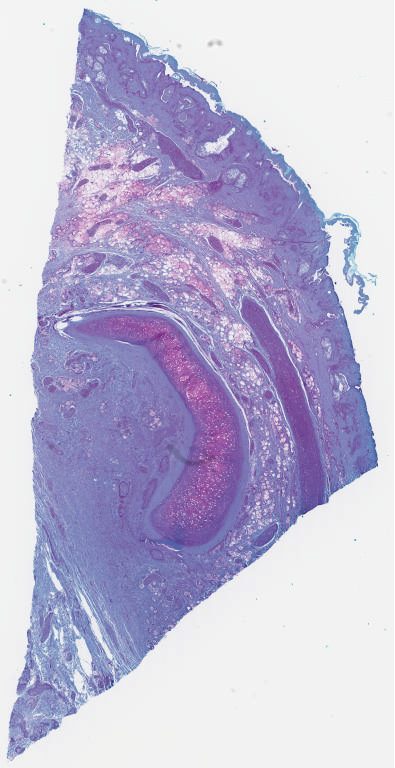

O - Trichrome.svs

34271 x 28944

@ 40X